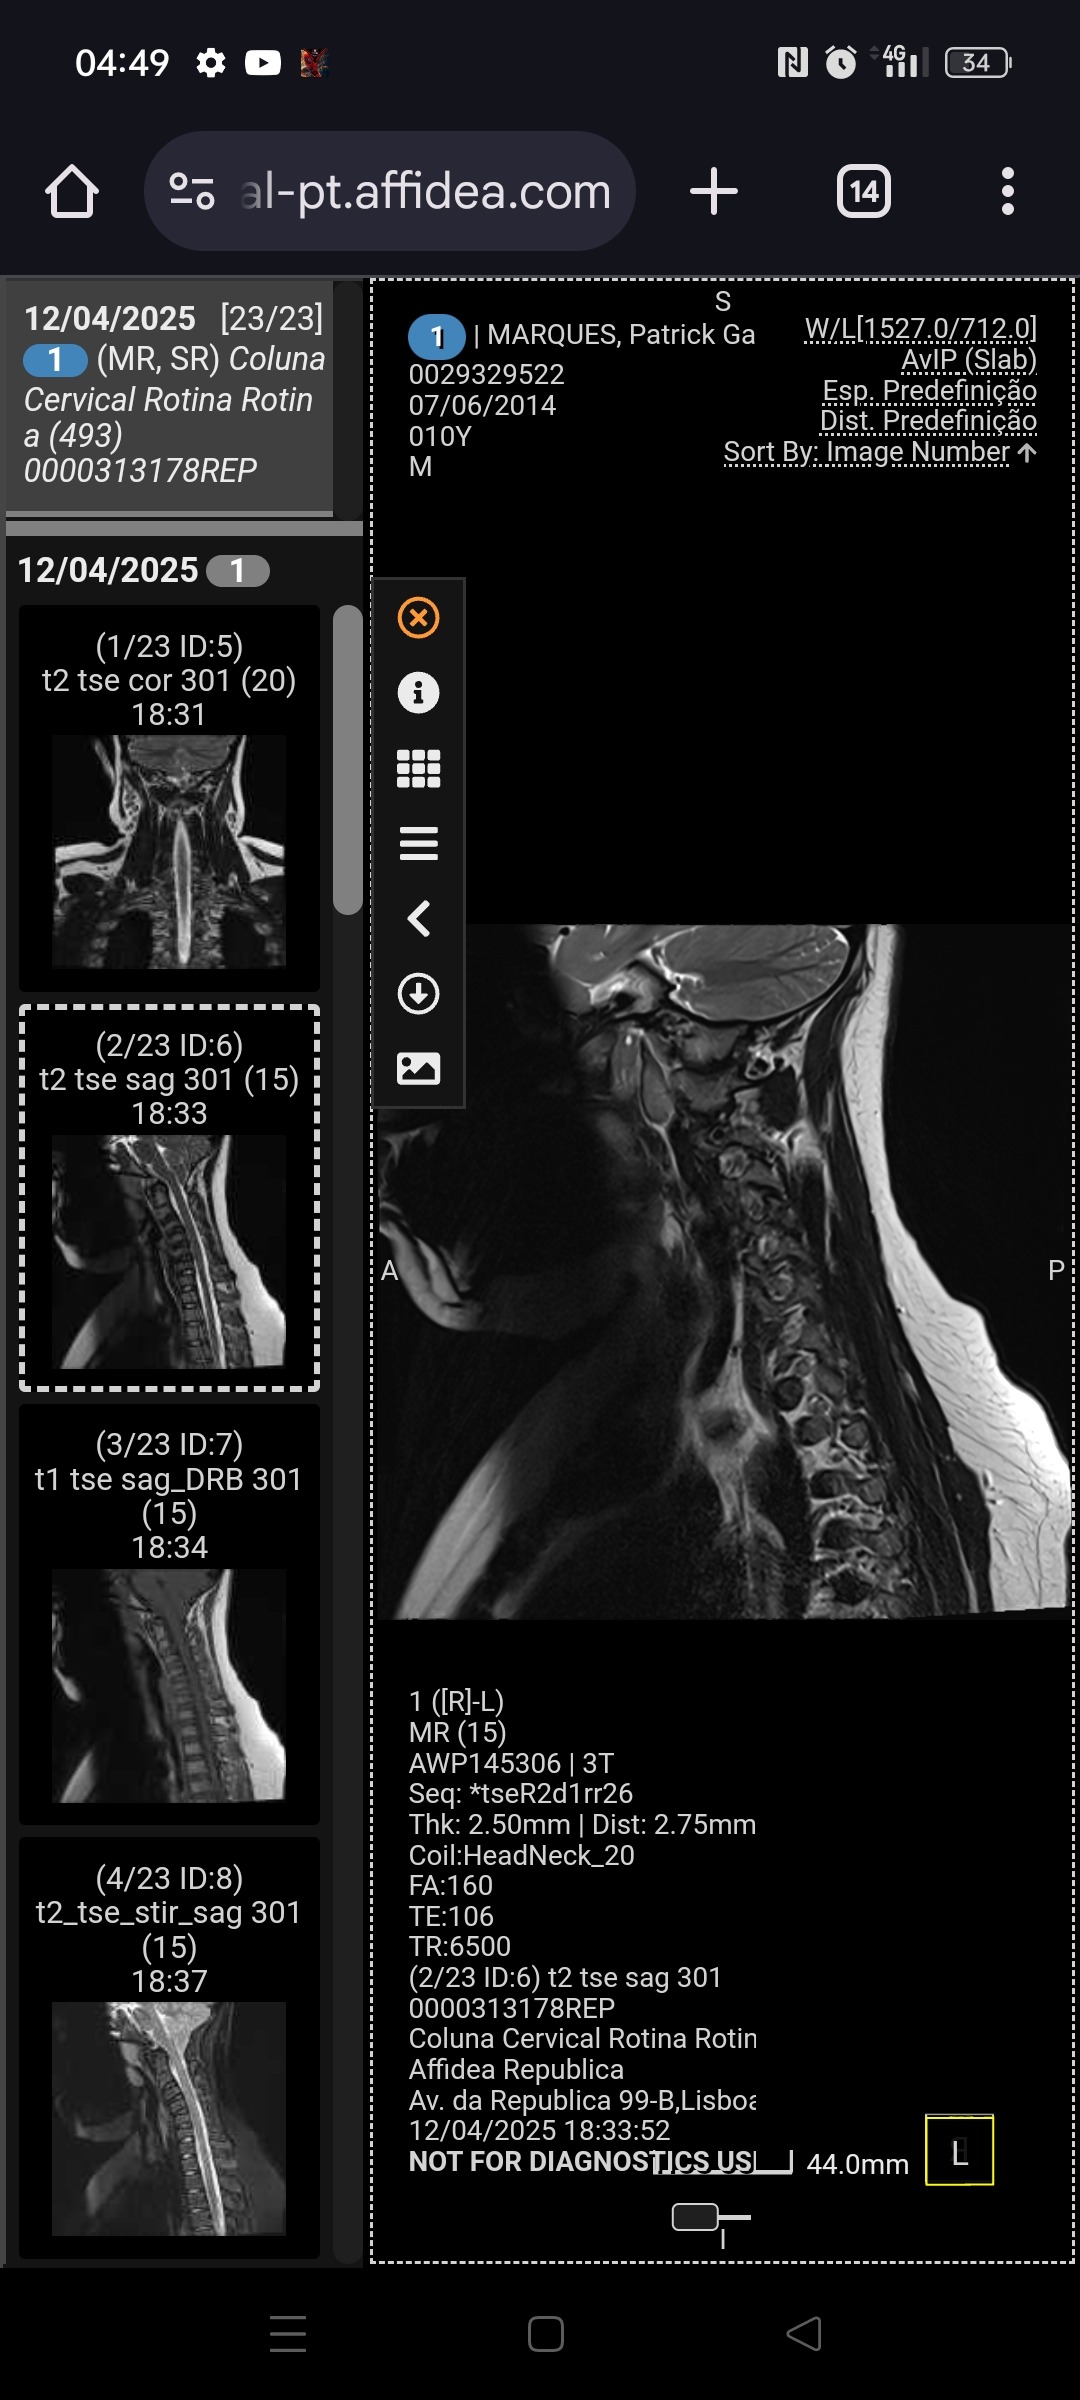

Mas em fevereiro recebemos um diagnóstico difícil: Malformação de Chiari tipo 1, uma condição neurológica que lhe causa dores, tonturas, perda de força e desmaios frequentes.